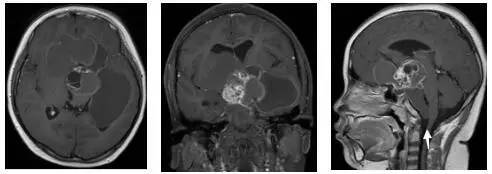

图2.术前MRI

白色箭头指示肿瘤下极达枕大孔区